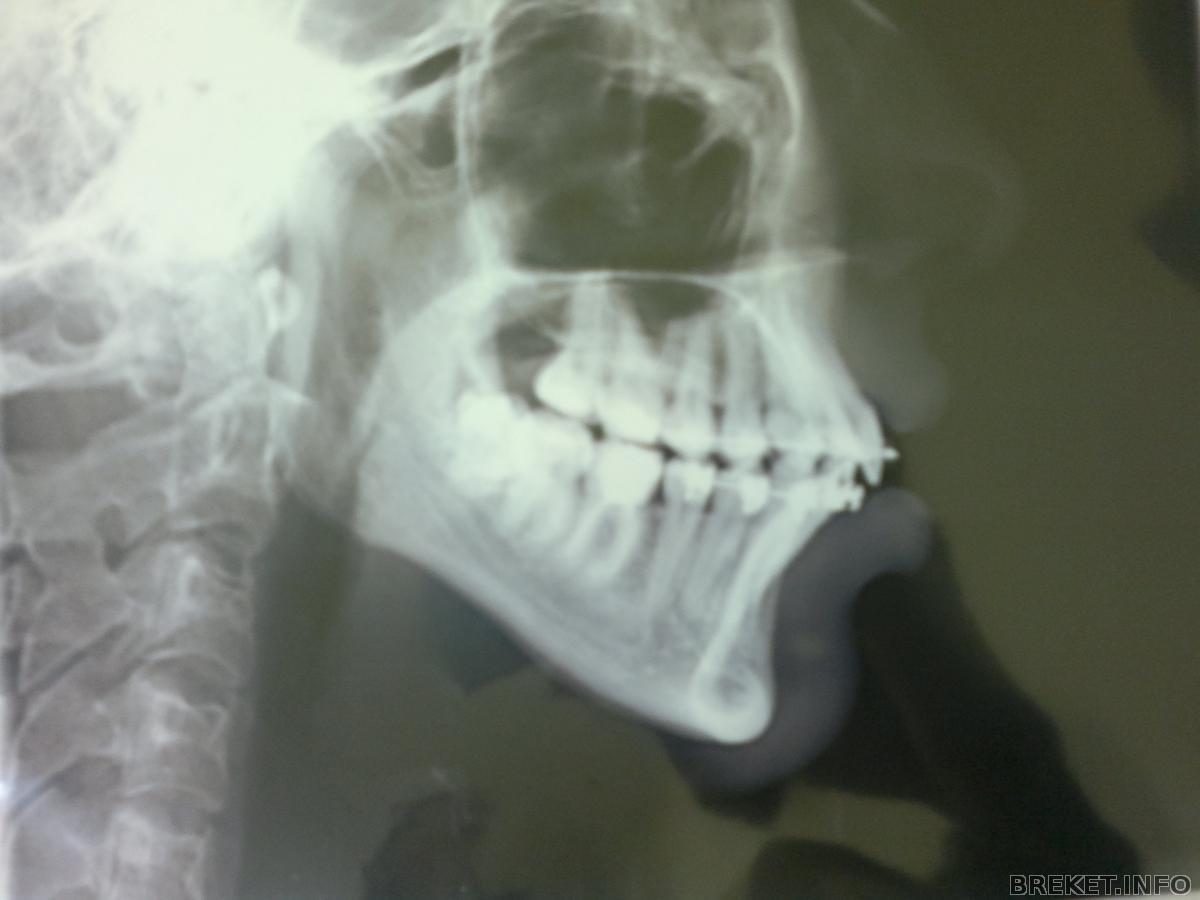

Такой наклон моих резцов (примерно)

По своим новым "снимочккам" в БС, я определила

(глаз-алмаз) что за год с хвостом, ничего не изменилось

Ближе